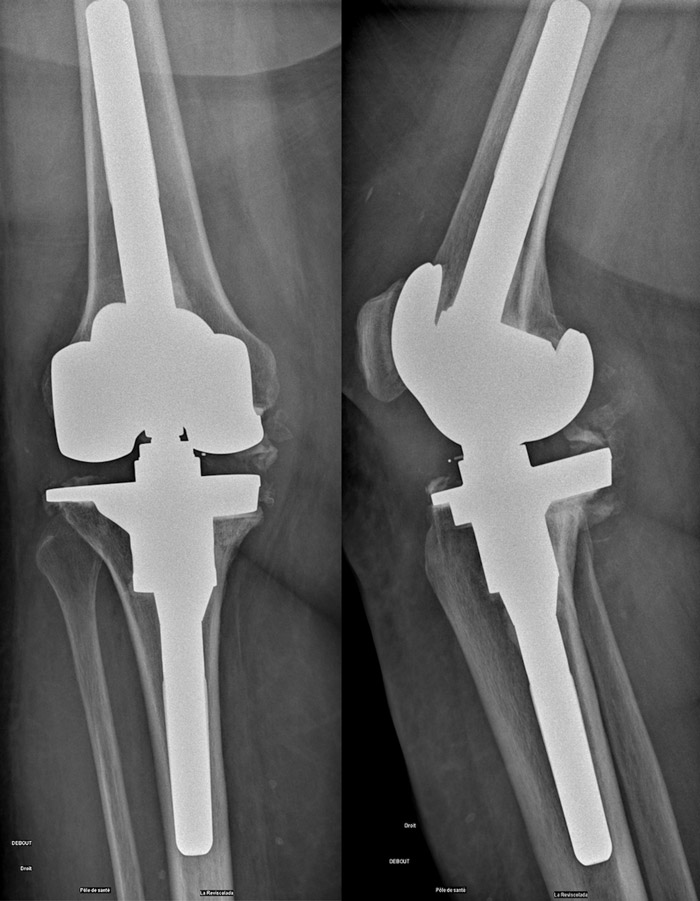

Post-operative X-Rays